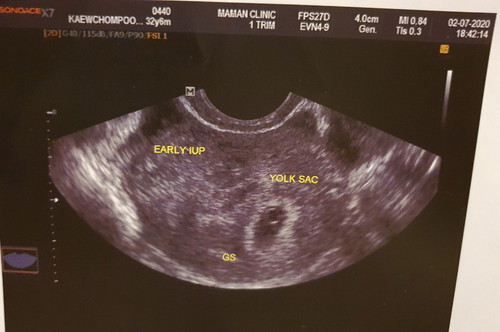

นับอายุครรภ์ตามประจำเดือนล่าสุดคือ 6วีค2วัน แต่พอซาวน์หมอบอกเล็กมาก น่าจะ5วีค วันนี้เจอถุงตั้งครรภ์กับไข่แดงค่ะ กลัวท้องลมมากค่ะ

5w น่าจะยังมองไม่เห็นค่ะ